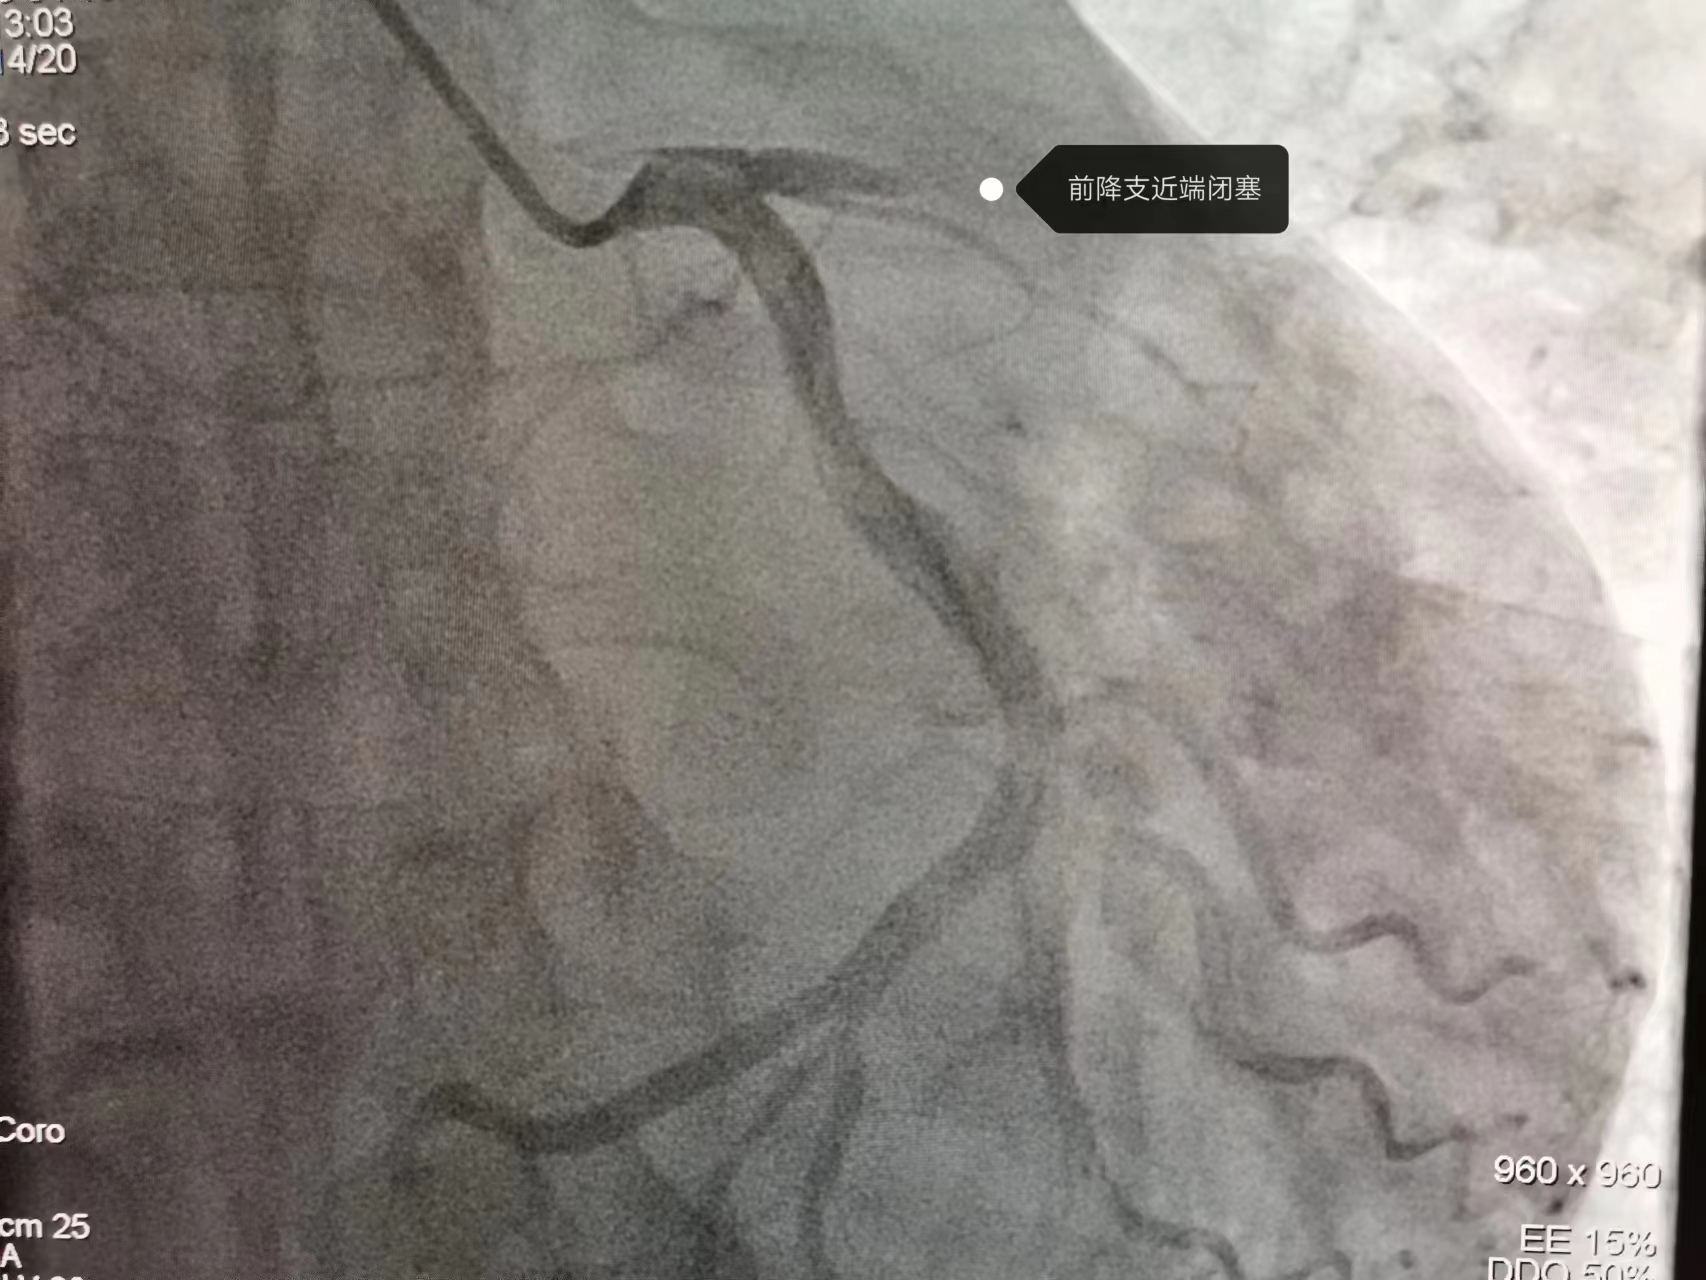

今年46岁、家住隘口乡的祝某,上午9:42在我院做心电图后没及时离开,随后说还有些不舒服,在心电图室再次做心电图提示急性广泛前壁心梗。然而,患者病情变化始料未及,10 时02分,患者突发意识不清,四肢抽搐,触摸大动脉搏动消失,患者呼吸心跳骤停。至此,一场与死神的赛跑拉开帷幕。临床电生理学中心主任李江琴和徐秀春、张敏医生轮流心肺复苏并立即启动院内发生ACS救治流程联系胸痛中心团队。在医务科主任贺叔书统一调度下,急诊科、ICU、麻醉科、导管室、心内科主任马成亮等胸痛中心专家团队十几名医护人员迅速展开救治,通力合作,上演了一场与死神赛跑的生死时速。大家紧张地忙碌着,给予电除颤7次、静脉推注抢救药、气管插管、呼吸机辅助呼吸等......经过一个多小时的抢救,患者自主心跳终于恢复、但仍然无自主呼吸。考虑随时有恶性心律失常及心跳骤停风险,在ICU行呼吸支持下转运至导管室。在导管室团队密切配合、麻醉科全麻呼吸支持下,马成亮主任带领张守刚、杨凯等医生行急诊PCI治疗。开通闭塞的前降支血管,植入一枚支架,术后患者心电图ST段下降>50%,TIMI血流恢复3级,患者心肌得到有效再灌注。

从上台至开通患者血管,仅用时29分钟,至此,此次抢救暂时告一段落,患者闭塞的血管再通,患者存活概率大大增加,术后转入ICU治疗。